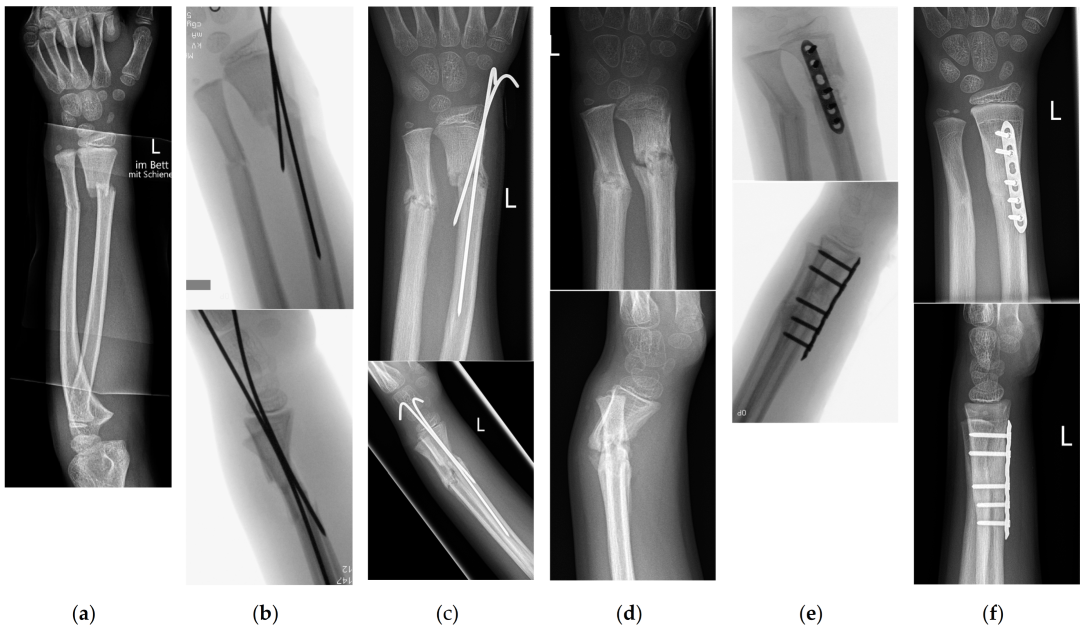

2. Materials and Methods

3.3. Type of Stabilization